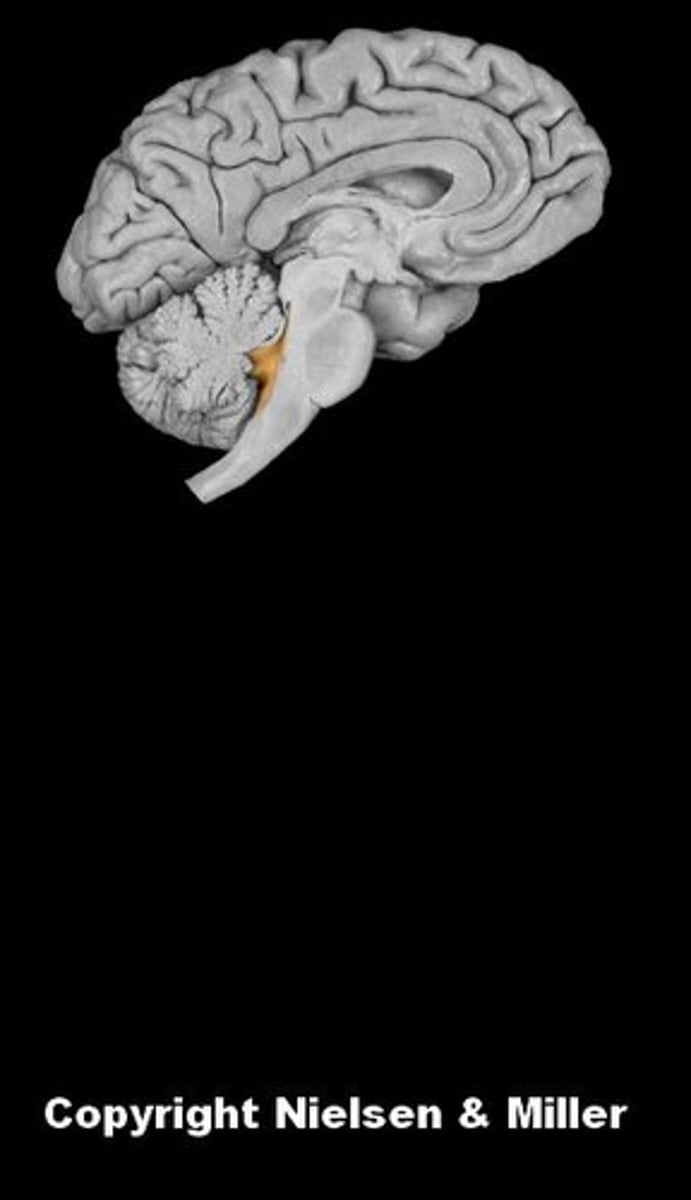

brain

cerebellum

cerebral hemispheres

cerebrum

fourth ventricle

hypothalamus

medulla oblongata

midbrain

pons